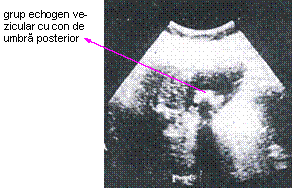

- echografia este astazi explorarea cea mai uzuala în patologia biliara, datorita urmatoarelor considerente: este metoda neinvaziva, este bine tolerata (nu exista inconvenientul iradierii sau al iodismelor, poate fi efectuata si în plin puseu al colecistitei acute repetându-se de câte ori este nevoie), este practicabila si la bolnavii cu bilirubinemia peste 3 mg%, permite stabilirea algoritmului mijloacelor diagnostice la bolnavii icterici (cai biliare nedilatate icter posibil medical; cai biliare intrahepatice dilatate se indica colangiografie transparietohepatica; CBP dilatata se indica ERCP), exploreaza concomitent si alte organe abdominale si depisteaza si alte leziuni ce ar putea fi implicate în suferinta biliara (chist hidatic hepatic, ciroza hepatica, pancreatita cronica sau chiar acuta, litiaza pancreatica, cancer de cap pancreatic etc.); limitele echografiei constau în lipsa de precizie a explorarii CBP (mai ales a coledocului retroduodenal);